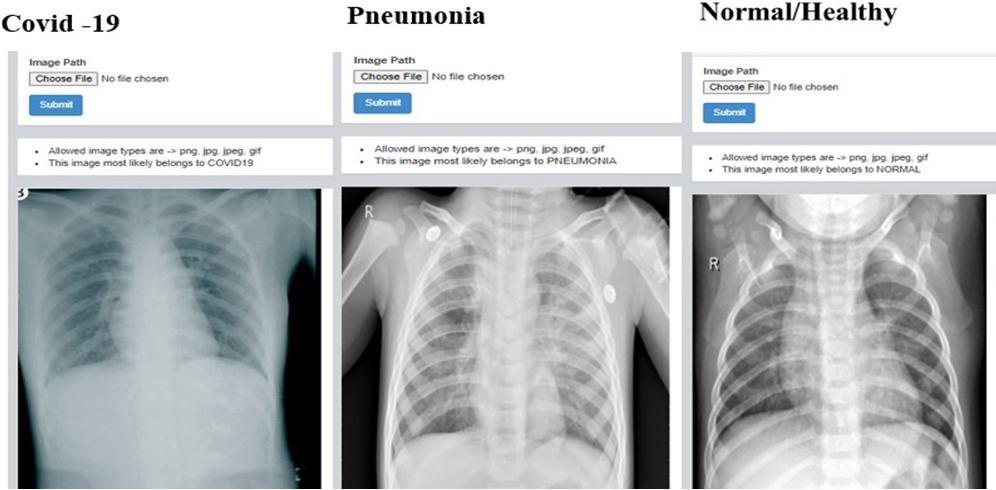

Fig. 2: Data set with three classes

It has 5144 total images, of which 460 are covid 19, 1266 are images of people who are healthy or normal, and 3418 are images of people who have pneumonia. Covid 19 isa recent infection, thus there aren’t many pictures of it. The data set is obtained from the Kaggle website and divided into two portions: 20% for validation and 80% for training.

G. Results of web application

1) Detection of Covid 19 , Pnuemonia and Healthy chest x ray: Here the X ray images are fed by clicking on choose file in dash board after that we need to select file in which the images are present and upload it once after uploading needto click on submit button once after the submiting image we can observe result whether the given X ray belong to covidor pneumonia or normal.The same procedure is followed for many iteration to check whether develop web application is accurate by feeding different types of X ray images.